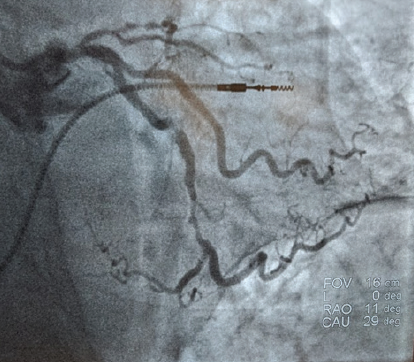

Cardiac catheterization upon her admission demonstrated severe in-stent restenosis of the LMCA, sequential high-grade stenosis (90%) of a tortuous mid–left circumflex artery, and a tandem severe distal circumflex coronary stenosis (Figure 1). These lesions represent a complex interventional challenge with delivery of balloons and stenting to treat the arterial coronary stenosis. The patient was deemed to be a poor candidate for redo CABG and she had failed optimal medical therapy including ß-blockers, long-acting nitrates, and calcium channel blockers.

The decision was made to proceed with percutaneous coronary intervention (PCI) using an extra backup guide and a balanced middle-weight wire (BMW) to cross the lesions in the left circumflex. From the onset of the procedure, the ability to deliver a balloon and subsequent stent appears to be arduous and difficult given the tortuosity and calcification of the left circumflex. With introduction of a Guidezilla™ support catheter (Boston Scientific Corporation), a 2-mm balloon and a 2.5-mm balloon were introduced with difficulty in performing balloon angioplasty. Despite balloon angioplasty, including a high-pressure noncompliant 3.5-mm percutaneous transluminal coronary angioplasty balloon in the left main coronary artery, stent delivery was challenging and complex. The introduction of the EluNIR™ coronary stent system (Medinol Ltd., distributed by Cordis, a Cardinal Health company) allowed adequate pushability and deliverability to cover both the distal-mid–left circumflex artery with two stents. The LMCA was also stented with a 3.5-mm EluNIR™ stent, resulting in an excellent angiographic result (Figure 2). The patient’s postoperative course was uncomplicated and she was discharged home the next day.